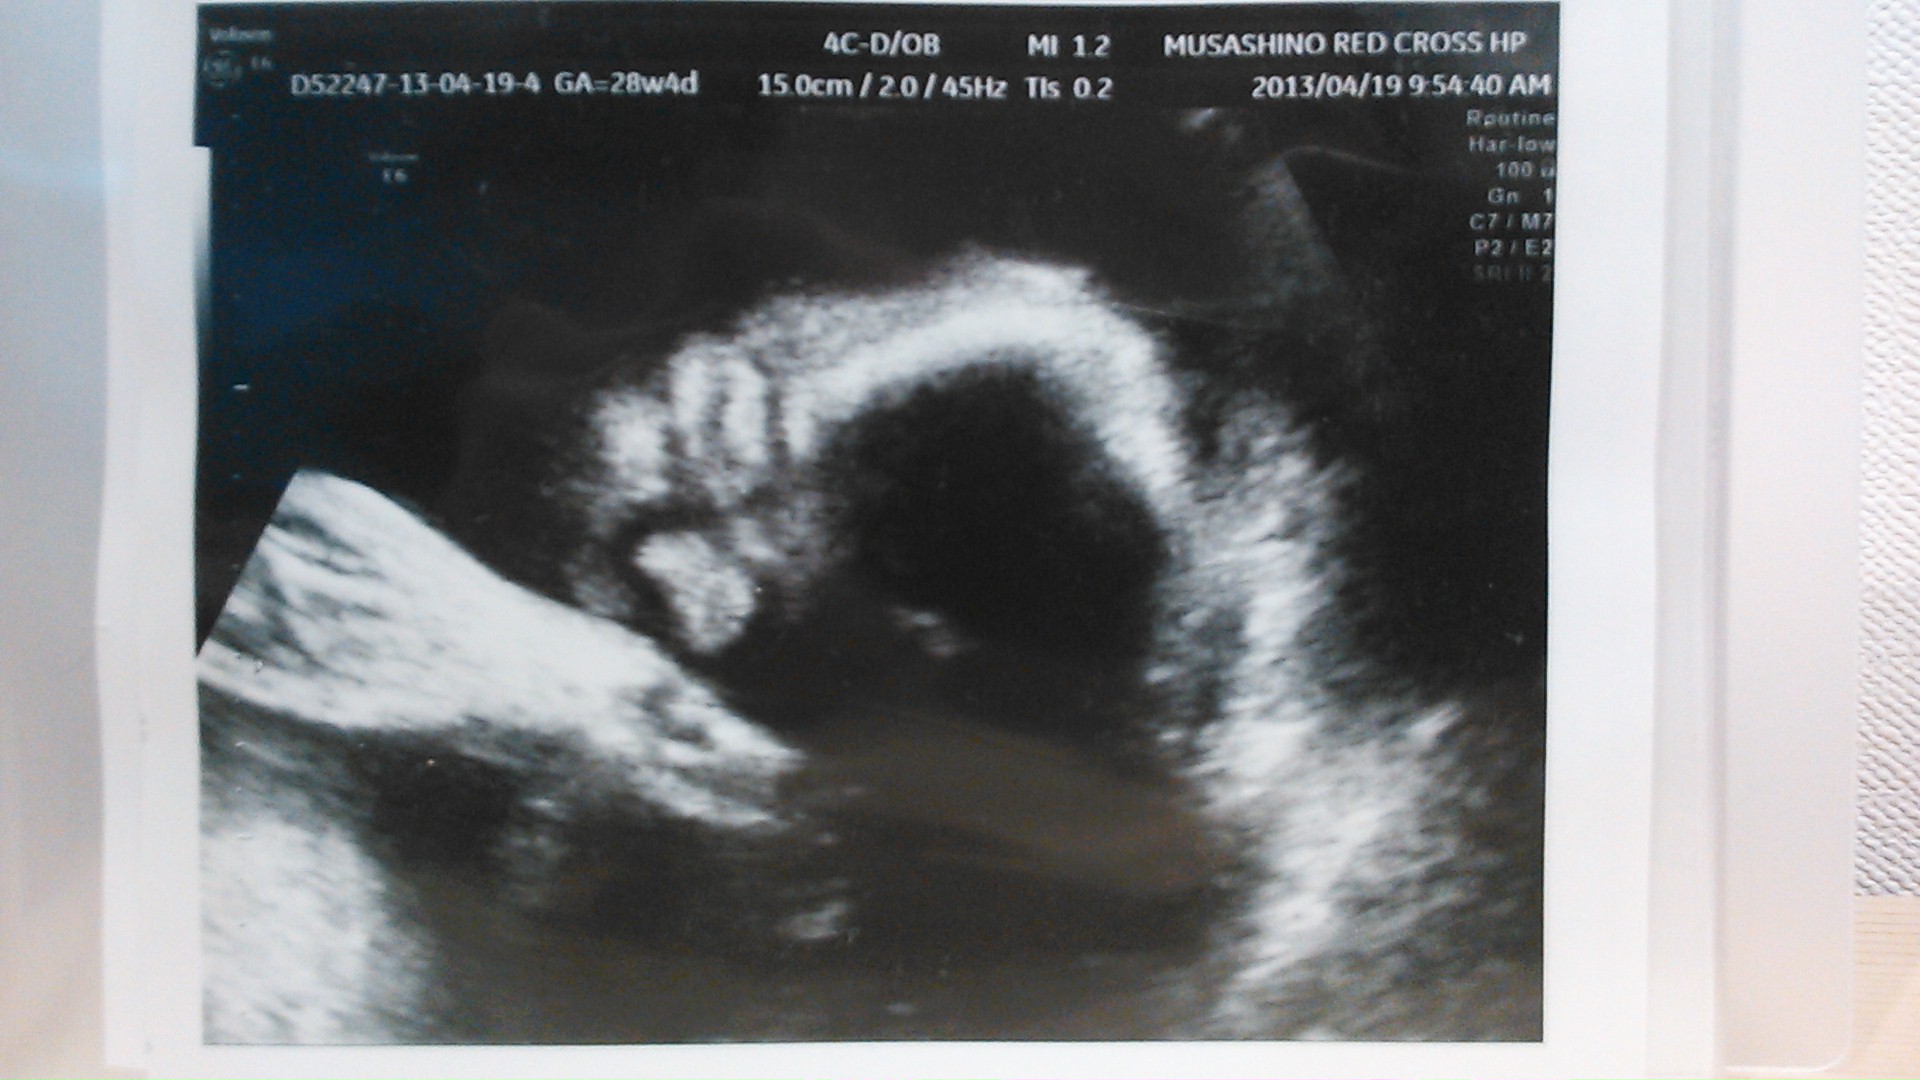

echo